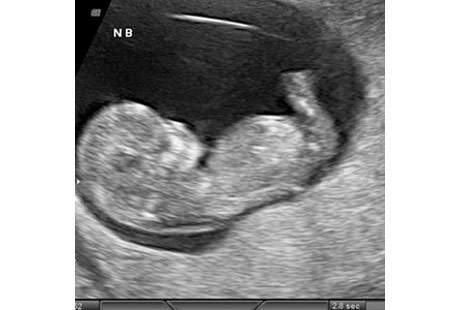

10. Minggu ke-11: Organ Genital Berkembang

Foto: AIUM.org

Di awal kehamilan 11 pekan atau 9 minggu setelah pembuahan, kepala janin yang masih terus disempurnakan bentuknya, memiliki ukuran sekitar setengah dari panjang keseluruhan. Untuk mengejar ketertinggalan, tubuhnya akan berkembang pesat dalam beberapa pekan mendatang. Nah, dengan bentuknya sekarang sudah bisa digambarkan sebagai janin.

Di pekan ini, dagu dan leher berkembang. Fitur wajah menjadi lebih jelas. Sementara itu telinganya bergerak lebih tinggi di kepala. Sel darah merah mulai terbentuk dalam hati janin. Pada akhir pekan ini, genitalia eksterna janin Anda akan mulai berkembang menjadi penis atau klitoris dan labia mayora.

Sel darah merah mulai terbentuk dalam hati janin. Pada akhir pekan ini, genitalia eksterna janin Anda akan mulai berkembang menjadi penis atau klitoris dan labia mayora. Sekarang panjang janin Anda dari puncak kepala sampai bokong sekitar 50 milimeter. Sementara itu beratnya hampir 8 gram.